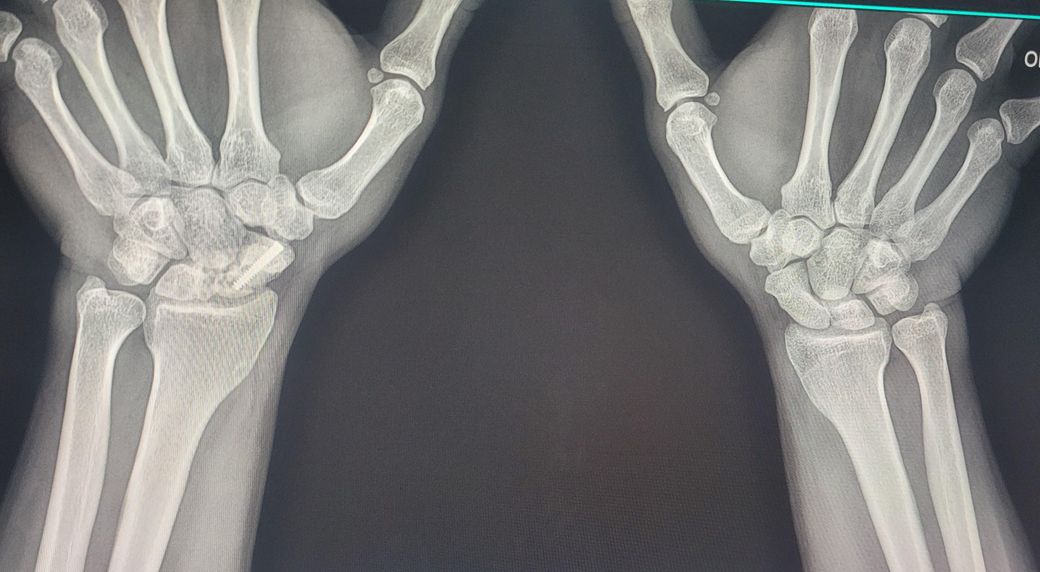

손목 주상골 골절로 인해 재수술을.해야할까요

20대 초반 조기축구를.하다 주상골 골절이 된지 모르고 방치하다 6개월 위 주상골 골절 판정 후 골반뼈 이식 및 철심넣고 6시간 대수술을 받았습니다. 그 후 너무 흉터도 크고 일상에는 지장없으나 현재 40살이 다되어 가끔 손목이 욱신거리곤 합니다. 다시 재수술을 받아야할까요? 재수술을 하더라도 불유합이 안생길까요? 걱정이 많습니다. 전문의 답변 부탁 합니다

• 2번 째 사진